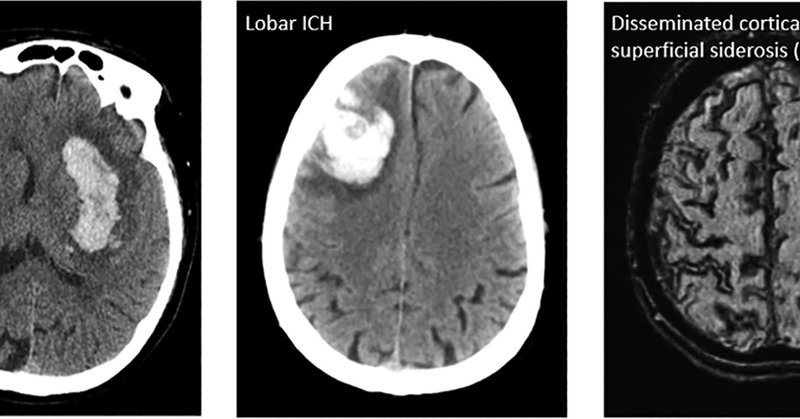

Cortical superficial siderosis – cortical iron deposition in #CerebralAmyloidAngiopathy – is associated with chronic neuroinflammation. A potential contributor to future hemorrhage #ICH risk? Congrats to @CorinneAAuger on her first author publication! https://t.co/dQb9EVr7PV

Background Cortical superficial siderosis (cSS) has recently emerged as one of the most important predictors of symptomatic intracerebral hemorrhage and is a risk factor for post-stroke dementia in...

Dami Adetunla presents our mouse model of cortical superficial siderosis at ISC! #CerebralAmyloidAngiopathy

How does vascular dysfunction progress in #CAA? See our pre-print which used a combo of in-vivo two-photon microscopy and MRI to track changes in #vasomotion, #pulsatility, #CBF, #CVR, and more!

Background Cerebral amyloid angiopathy (CAA) is a cerebral small vessel disease in which amyloid-β accumulates in vessel walls. CAA is a leading cause of symptomatic lobar intracerebral hemorrhage...